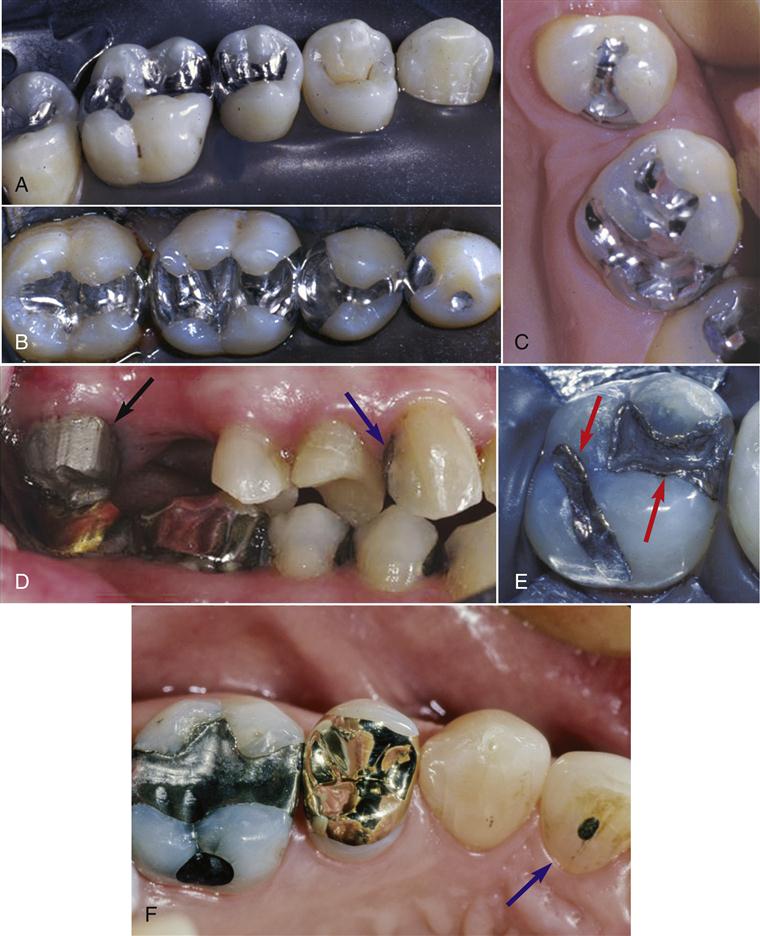

2.根据嵌体材料分类

(1)金属嵌体:有贵金属及非贵金属合金嵌体。金合金化学性能稳定,有良好的延展性能和机械性能,是制作后牙嵌体理想的传统修复材料(彩图3—10)。

(2)树脂嵌体:采用高强度复合树脂材料在模型上加工成形或CAD/CAM成形,调磨抛光后用树脂粘接材料粘接于牙体组织上。树脂嵌体为牙色修复体,易修补,对对拾牙磨耗小,美观性好。

(3)瓷嵌体:采用陶瓷材料在模型上加工成形或CAD/CAM成形,用树脂粘接材料粘接于牙体组织上。不同陶瓷材料有不同的加工工艺,如直接在耐火材料代型上制作的烤瓷嵌体;CAD/CAM磨削出的瓷嵌体;在模型上做熔模包埋后热压铸成形的铸瓷嵌体;采用金沉积法制作组织面衬底后做的烤瓷嵌体。瓷嵌体具有优良的美学性能。